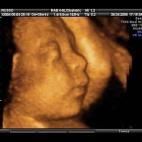

En esta galería puedes ver en fotos como es el desarrollo de un feto de semana en semana:

Desarrollo del feto, en fotos